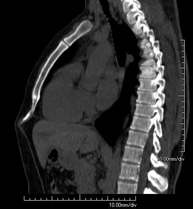

- Abdominal aorta CT angiography

A non-invasive diagnostic test that involves studying the abdominal aorta by obtaining high-definition anatomical images using CT (computed tomography) equipment and iodinated contrast. With the aid of workstations specialised for arterial studies, the image quality supports 2D and 3D reconstructions. It is indicated in patients with vascular disease (atherosclerosis), aortic aneurysms, abdominal pain of possible vascular origin, pre-surgical studies of lesions adjacent to the abdominal aorta as a vascular ‘map’, etc. Information obtained non-invasively is indispensable for patients requiring percutaneous or surgical processing. In patients who only require tracking of vascular lesions, this technique is the non-invasive technique of choice, together with MRI angiography.